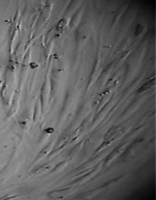

Исследование проведено на первичных культурах дермальных фибробластов и мезенхимальных стромальных клетках человека 4-12 пассажа.

Культуру дермальных фибробластов получали из кожно-мышечной ткани, а культуру мезенхимальных стромальных клеток – из фрагментов крыши черепа абортусов сроком 6-10 недель методом первичных эксплантатов (рис. 1, 2).